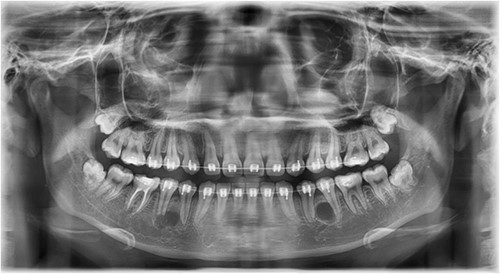

In this context, a buccal approach using a Neumann full-thickness flap was preferred (Fig. 4). When a buccal approach is planned, then the location of the mental nerve must be identified to avoid any post-operative sensory problems. The most challenging part is to exercise extreme caution during Ostectomy to avoid damage to the adjacent tooth roots.